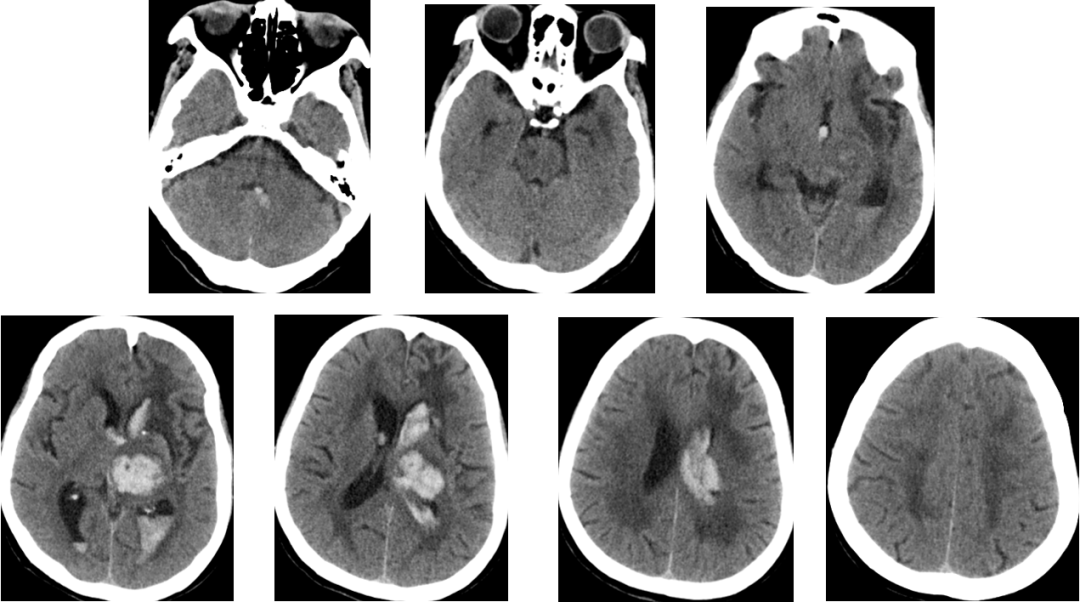

2014-11-19 CT

2014-11-20 CT

再出血?

脑水肿?

脑积水?

腰大池过度引流?(非高颅压脑疝)

2014-11-24 CT

气颅、轻度脑积水,加强脱水,必要时用激素

腰大池引流白天50ml,降低引流管高度,在半个小时左右突然100多ml,颜色由淡红转为鲜红色,继而意识障碍加重有昏睡转为浅昏迷,收缩压升高到200mmHg。

非高颅压脑疝!

加强脱水!

患者1小时后清醒。